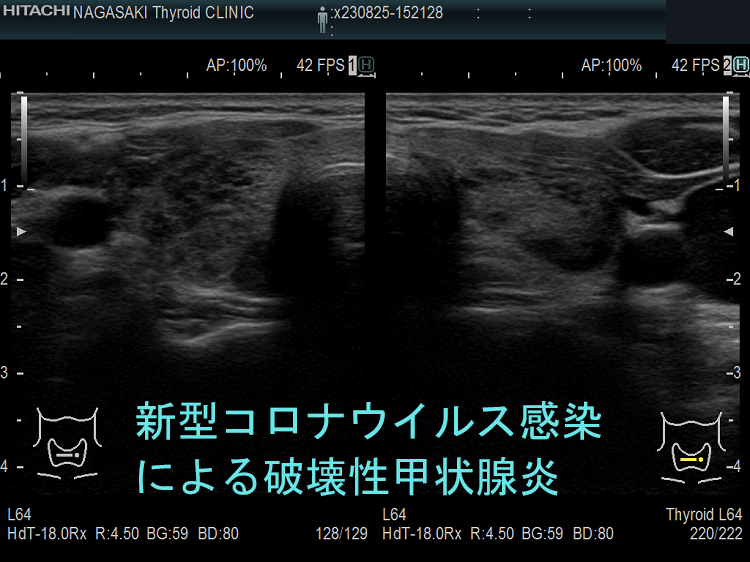

下の写真は、新型コロナウイルス肺炎に罹った甲状腺機能正常橋本病患者の感染前後計12か月の超音波(エコー)画像です。新型コロナウイルス肺炎になる6か月前と6カ月後に、1年に1回の定期検査で長崎甲状腺クリニック(大阪)を訪れていました。新型コロナウイルス肺炎発症時の甲状腺機能は不明ですが、少なくとも6カ月後は正常でした。しかし、発症前に比べて甲状腺は腫大し、腹側(写真下部)の低エコー領域(黒い部分)が拡大しており、橋本病の炎症が増悪したと推察されます。新型コロナウイルス肺炎発症時には破壊性甲状腺炎(無痛性甲状腺炎)を起こしていても不思議ではありません。

以下は、長崎甲状腺クリニック(大阪)の自験例です。

長崎甲状腺クリニック(大阪)の自験例

急性期

1.5か月後

5か月後